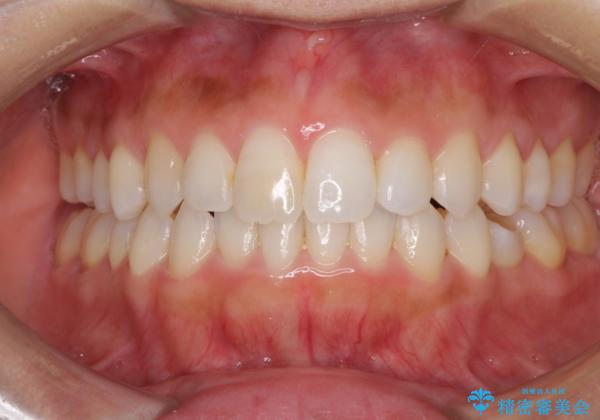

前歯の叢生を治したい インビザラインによる矯正治療

- 上下の前歯のデコボコと奥歯の反対咬合を気にして来院された患者様です。

インビザラインを用い、上下顎ともにIPR(歯と歯の間を削る)により叢生を改善することとしました。

奥歯の反対咬合は、骨格に由来するものであるため、改善できるところまで改善していくこととしました。

治療を長期化させたくないとのご要望があったので、左下の90度捻転した歯は、捻転した状態のゴールとしました。

反対咬合を改善したことで、歯ぎしりしたときの引っかかる感じがなくなり、奥歯への負担を大きく軽減することができました。